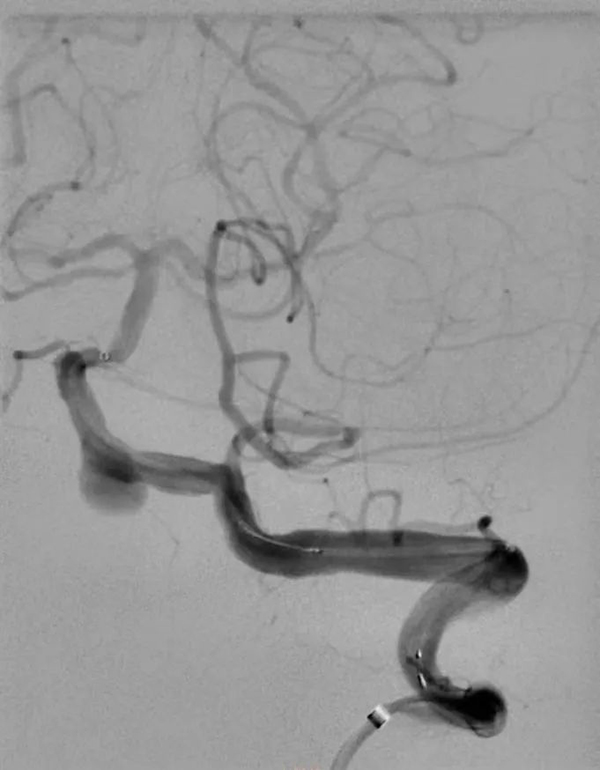

在市十院介入科团队、神经内科团队和医大二院神经外科团队共同努力下手术非常顺利,术中选用5F猪尾造影管开始进行主动脉弓造影和旋转造影见椎动脉V4段动脉瘤。选取工作角度,应用导丝超选至基底动脉,选用3.5*20mm pipeline II支架,定位释放。术后造影显示瘤体内血流灌注延迟缓慢。

导丝通过中